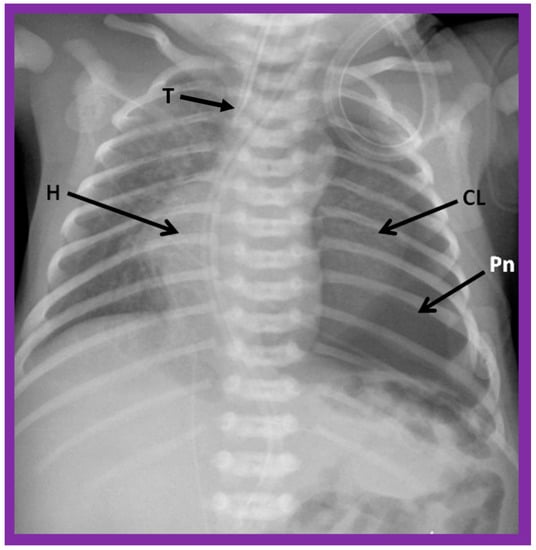

Figure 6. A chest roentgenogram of a baby illustrating dextroposed heart (H) due to left pneumothorax (Pn) pushing the heart into the right side of the chest. A collapsed left lung (CL) is pointed out. The trachea (T) is seen to deviate to the right. Modified from reference [4].

Figure 7. A chest roentgenogram of an infant demonstrating dextroposed heart (H) secondary to diaphragmatic hernia on the left side. The abdominal contents, including intestines (In) are relocated to the left side of the chest because of the diaphragmatic defect, pushing the heart into the right chest. The trachea (T) is displaced to the right. ET, endotracheal tube. Reproduced from reference [4].